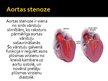

Aortas stenoze

Aortas stenoze

Aortas stenoze